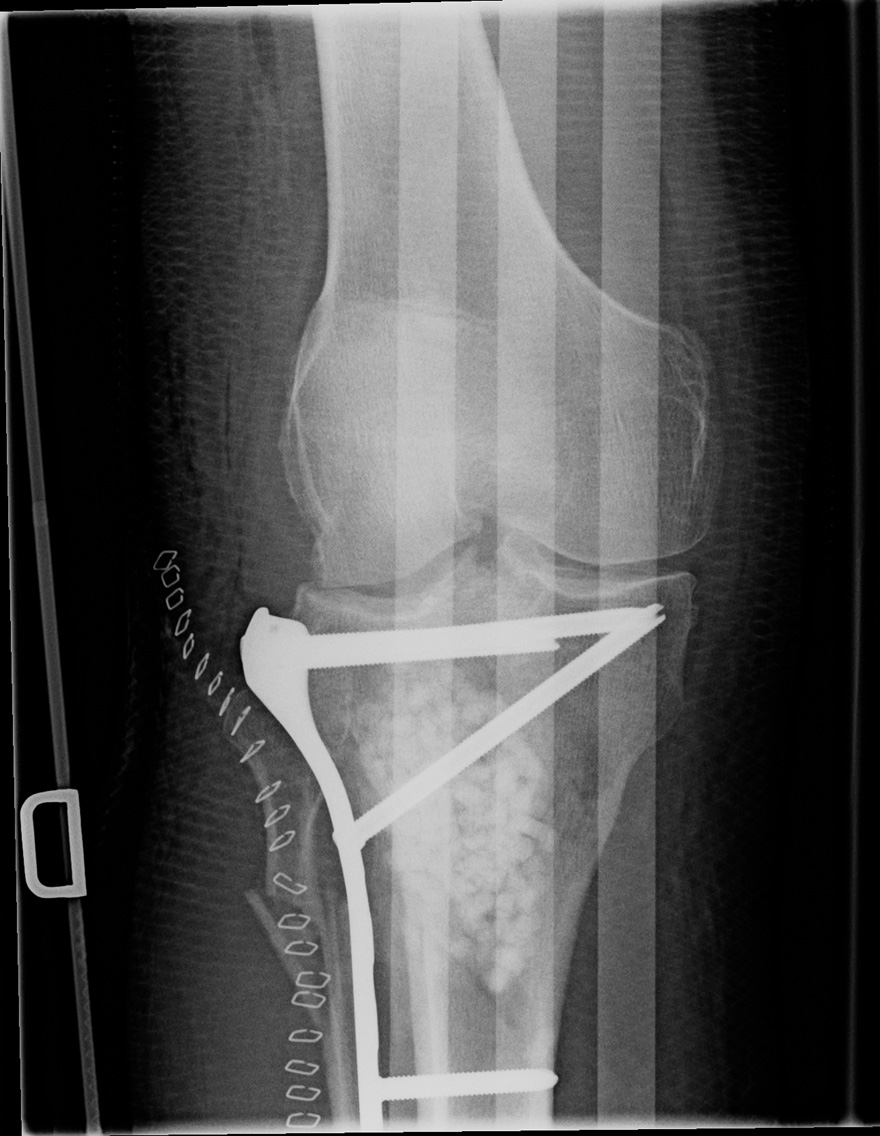

64-year-old male:

Postoperative control of a Schatzker type 6 tibial plateaux fracture.

Locked plate and screws

Open reduction of a Schatzker type 6 fracture and fixation with a locked plate and screws on the lateral side of the tibia.

Decreased lateral joint space and a 12° valgus alignment.

Bone graft

Bone graft installed during the surgical procedure.

Fibular fracture

The fibular fracture was not addressed.

Metallic staples

Staples for the surgical incision closure.